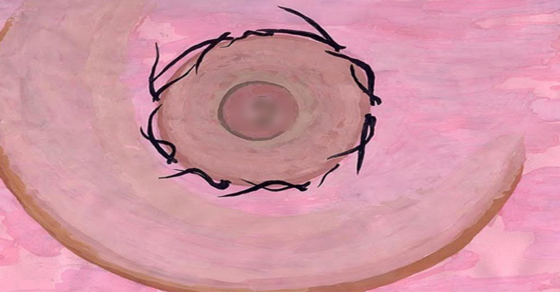

ما هو سبب ظهور الشعر في حلمة الصدر؟

قد تعاني بعض السيدات من ظهور نمو الشعر في الأماكن الغير المناسبة في الجسم خاصة في منطقة الثدي مما يجعلها متوترة و تشعر بالحرج منها و تفقدها الثقة بالنفس. فإذا كنت تعانين من هذه المشكلة الصحية و لا تعلمين سبب ظهورها، فتابعي معنا هذا المقالي لنوضح لك أسباب نم والشعر في حلمات الثدي و حولها و في الأماكن الأخرى الغير المناسبة للجسم مثل الذقن و منطقة البطن و الأذن.

ما هي أسباب نمو الشعر في الحلمات و المناطق الأخرى؟ أولا: أبرز سبب لنمو الشعر حول الحلمات أو الذقن أو الأذن أو في منطقة البطن لدى المرأة هو الاضطرابات الهرمونية التي تحدث خلال فترة الحمل أو في مرحلة سن اليأس بعد انقطاع الطمث.

ثانيا: تناول بعض أنواع الأدوية التي تسبب خلل في إفراز الهرمونات الأنثوية و الذكرية في الجسم أو التي تزيد من نسبة هرمون التستوستيرون في الدم و مشتقات الكورتيزون. ثالثا: إصابة السيدة بالشعرانية و هي التي تسبب زيادة نمو الشعر في الأماكن التي ينمو فيها عادة عند الرجال في الجسم مثل الشنب و الذقن و البطن و حلمات الثدي و لا يعني ذلك بالضرورة زيادة في الهرمون الذكري في الجسم و إنما قد يكون ذلك بسبب فرط تفاعل بصيلات الشعر في هذه الأماكن.

رابعا: الإصابة بتضخم في الغدة الكظرية بالجسم حيث توجد هذه الغدة فوق الكليتين في الجسم مما يزيد من إفراز هرمونات الذكورة في الجسم. خامسا: وجود تكيس في المبيض مما يؤدي أحيانا إلى تكوين حويصلات أو أكياس داخله و بالتالي تولد الخلايا التي تسبب زيادة إفراز هرمون الذكورة في الدم و بالتالي يظهر الشعر بغزارة في مناطق غير مرغوب بها في الجسم و الوجه و الساقين و الصدر.

سادسا: الشعور بحالة من الغضب و الانفعالات العصبية و التي تؤثر على عمل الغدة النخامية في الجسم و بالتالي حدوث خلل في الإفراز الهرموني في الجسم و نمو الشعر في النهاية. سابعا: الإصابة بالسمنة المفرطة كذلك قد تكون سببا في ظهور الشعر في الأماكن الغير مرغوب بها في الجسم.

ما هي أنواع الشعرانية؟ النوع الأول: يطلق عليه اسم شعرانية النسق الذكوري و هي موجودة بنسبة 90 بالمائة من حالات الشعرانية و هي تحدث بسبب الخلل الهرموني في جسم الفتاة. النوع الثاني: و يطلق عليه التشعر و هو غالبا يكون بسبب وراثي و ليس له علاقة باضطرابات الهرمونات في الجسم.